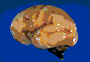

3.Coupe anatomique des hémisphères cérébraux à 14 SA.